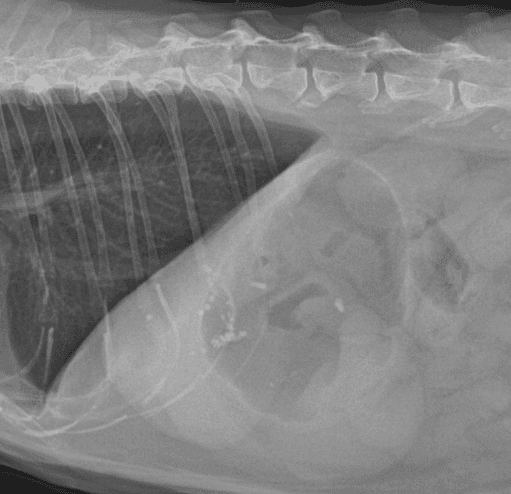

간, 담도 수술은 수술뿐만 아니라, 수술 후 중환자 관리도 중요하기 때문에 외과와 내과의 협진이 매우 중요합니다. 동탄시티동물의료센터에서는 최신 수술 장비의 도입으로 간담도 수술에서 출혈 및 부작용을 최소화 하였으며, 수술 후 협진 시스템을 통해 수술 후 관리에도 최선을 다하고 있습니다.

간종양

담석

담낭점액종

0164 채널 CT 촬영을 통해서 신속하게 고화질 영상을 얻어, 종양 유래 확인 및 전이 평가, 간문맥단락증(PSS), 선천적 뼈 기형과 같은 심화된 진단을 할 수 있습니다.

04흉복부, 골격계 전반의 선명하고 우수한 영상을 저선량으로 촬영이 가능

05선명한 초음파 영상 심장/응급초음파 포함, 장기 내부이상에 정확, 빠른 진단이 가능